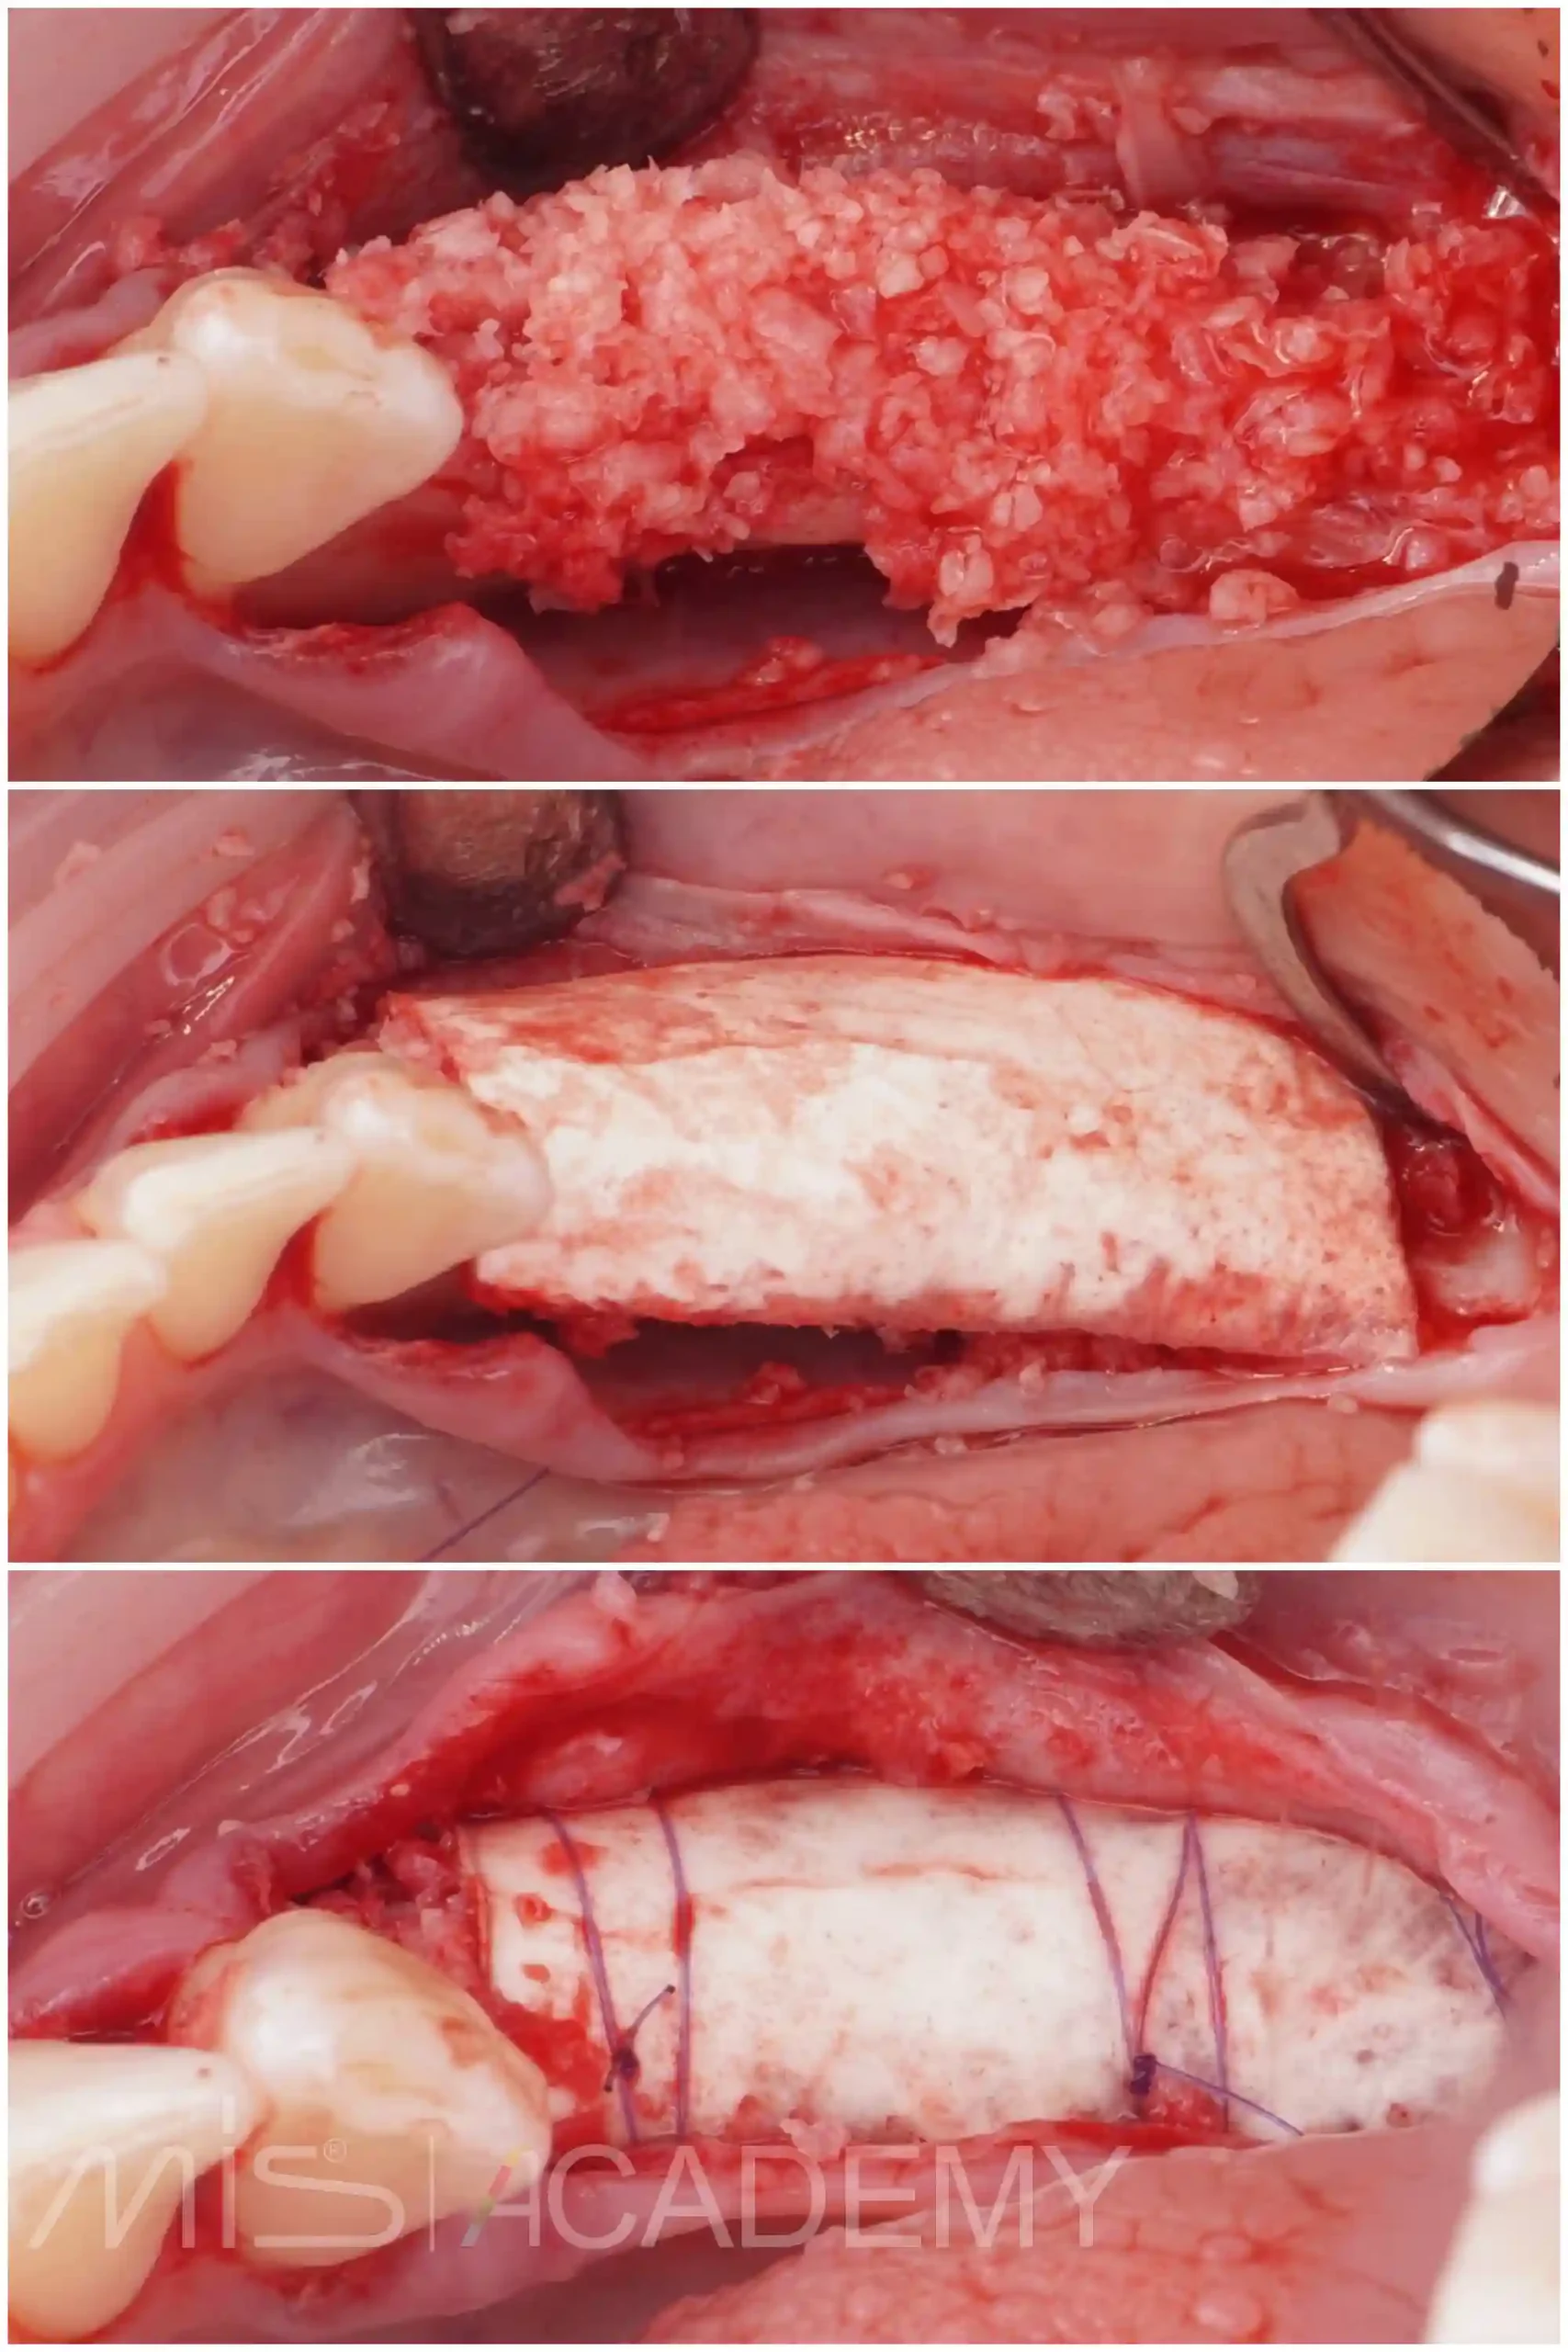

— Gen-os.

— Ауто и ксено Lamina curved, которая была зафиксирована надкостничными швами.